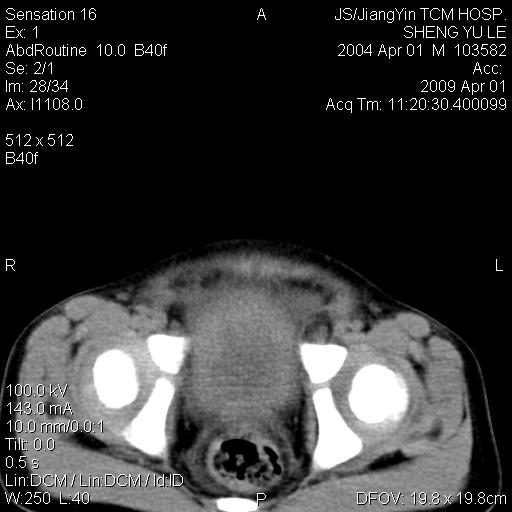

m,5岁。尿痛尿频数天。既往无病史。ct平扫腹盆腔积液。膀胱壁明显增厚。另可见心包增厚。wbc5万,骨髓穿等结果。请指教。

膀胱影像表现结合临床应该是急性膀胱炎症,但为什么有腹水呢?双肾输尿管无扩张,泌尿系压力应该不大不至于引起尿外渗,应该是腹膜感染引起的,但楼主没有提及相关症状,腹膜及膀胱结核?患者白细胞5万(结核不至于这么高啊),脾脏增大,是不是有白血病?进一步检查。。

腹水,膀胱壁增厚,wbc5万,结合临床,支持感染性疾病---感染性腹膜炎、腹水,急性膀胱炎,败血症。期待结果。